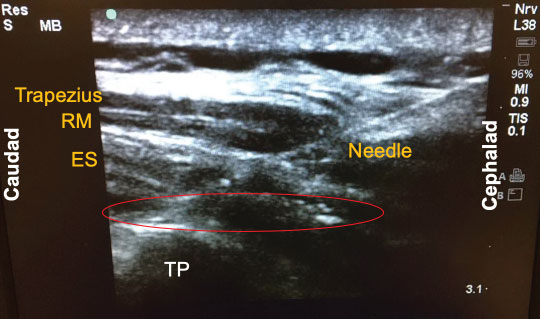

Since its introduction a few years ago, there have been numerous descriptions published on how to perform the ESP block. The following is a brief summary of the technique used to perform the block on our previously-described patient. With the patient in the sitting position, a high-frequency linear ultrasound probe was placed longitudinally on the patient's back approximately 3 cm lateral to the 5th thoracic (T5) spinous process. Three muscles above the hyperechoic transverse process were identified: trapezius, rhomboid major, and erector spinae in order of superficial to deep layers (Figure 1). A 10-cm 18-gauge Tuohy needle was inserted in-plane with the ultrasound beam at a 30° angle in a cephalad to caudal fashion. The tip of the needle was directed to the myofascial plane between the erector spinae muscle and the T5 transverse process (Figure 2). Following negative aspiration of blood, 20 mL of 0.25% ropivacaine was incrementally injected. Linear fluid spread deep to the erector spinae muscle was visualized in real-time. Finally, for continuous postoperative infusion, a 20-gauge catheter was threaded through the Tuohy needle and secured at the skin with a goal of having 5 cm of catheter left in the myofascial plane.

Figure 1: Three muscle layers for the erector spinae plane (ESP) block: Trapezius, rhomboid major (RM), and erector spinae (ES).